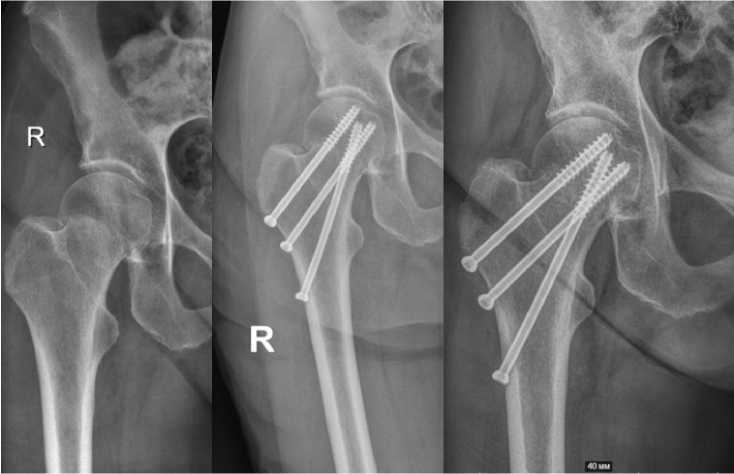

Рисунок 3. Сращение перелома с латерализацией винтов, АВН, укорочение

Figure 3. Fracture union with screw lateralization, AVN, shortening

Ключевым рентгенологическим преимуществом метода BDSF стало значимое снижение частоты и степени укорочения шейки бедра, а также варусной деформации. Этот факт имеет принципиальное значение, так как укорочение шейки и варусный коллапс являются не просто рентгенологическими находками, а прямыми предикторами неудовлетворительного функционального результата, приводя к хромоте, слабости абдукторов и болевому синдрому [18]. Объяснением этому служит предложенная Filippov биомеханическая концепция: дистальный опорный винт, установленный под большим углом с двойной опорой (калькар + диафиз), работает как балка, эффективно передавая нагрузку с головки на диафиз и разгружая губчатую кость шейки. Это предотвращает микроподвижность и вторичное смещение костных отломков в зоне перелома, что и является причиной укорочения при стандартной фиксации.